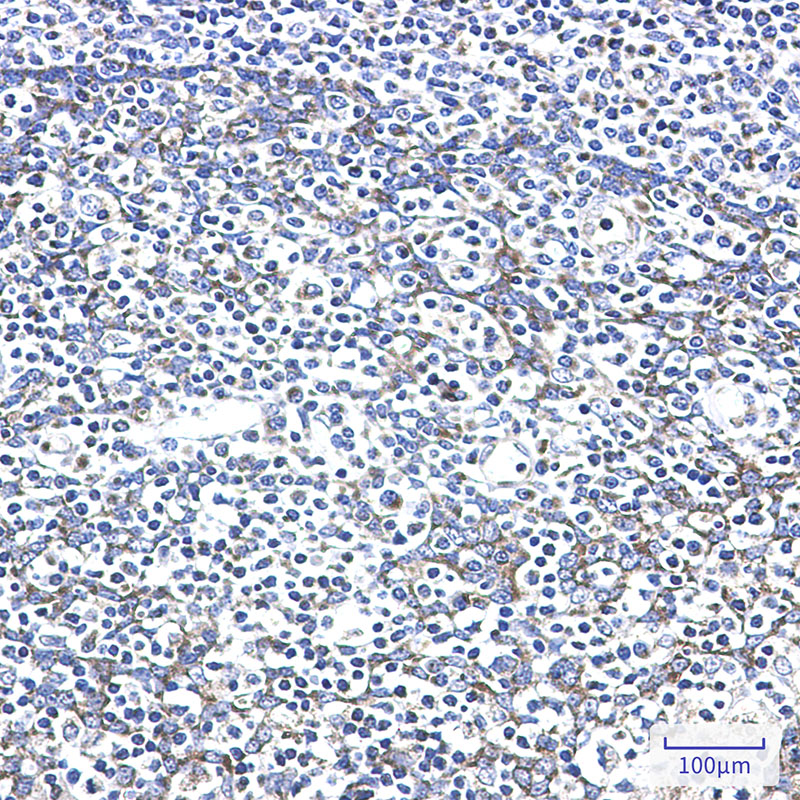

- Immunohistochemistry analysis of paraffin-embedded Human tonsil using AK2 antibody. High-pressure and temperature Sodium Citrate pH 6.0 was used for antigen retrieval.